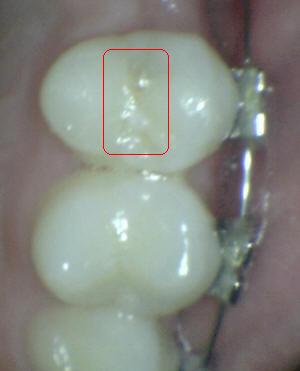

¿Determine los códigos pertinentes a cada imagen?

Click en el hipervínculo: Para comparar el resultado de su diagnóstico